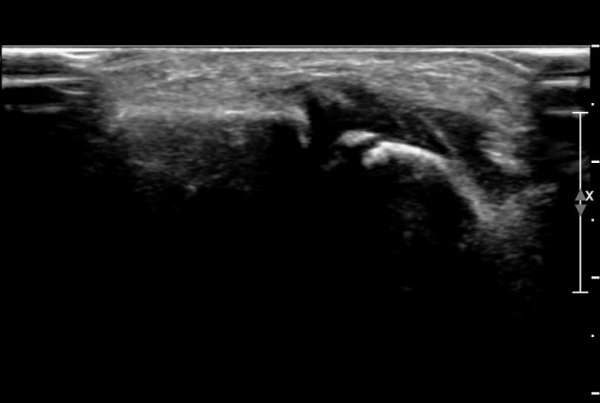

¾Õ°æ°ñºñ°ñÀδë Á¾´Ü¸é°Ë»ç¿¡¼­ °æ°ñºñ°ñÀδëÀÇ  Àú¿¡ÄÚ  ºÎÁ¾ ¹× ÀδëºÎÂøºÎ °æ°ñÀÇ

°ß¿­°ñÀýÀÌ  °üÂûµÊ(»çÁø 2, 3, 4)